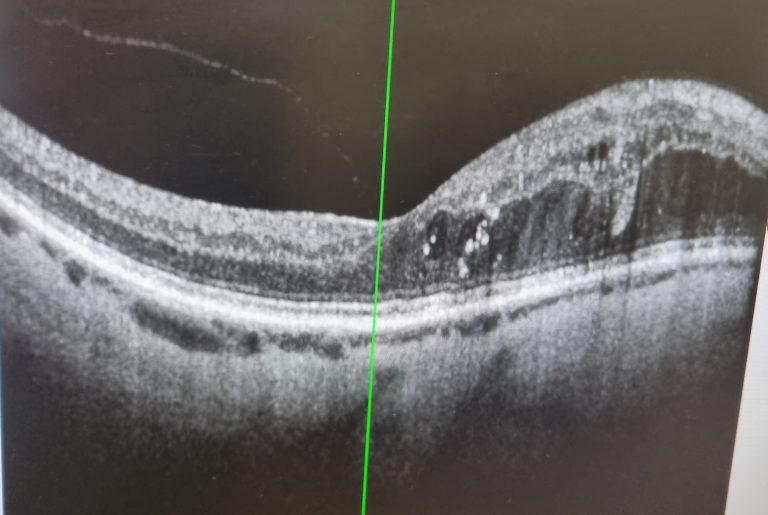

A noted previously, my diabetes was first identified during a visit to the optician. My GP, besides prescribing treatment, also referred me to ophthalmology to monitor my...